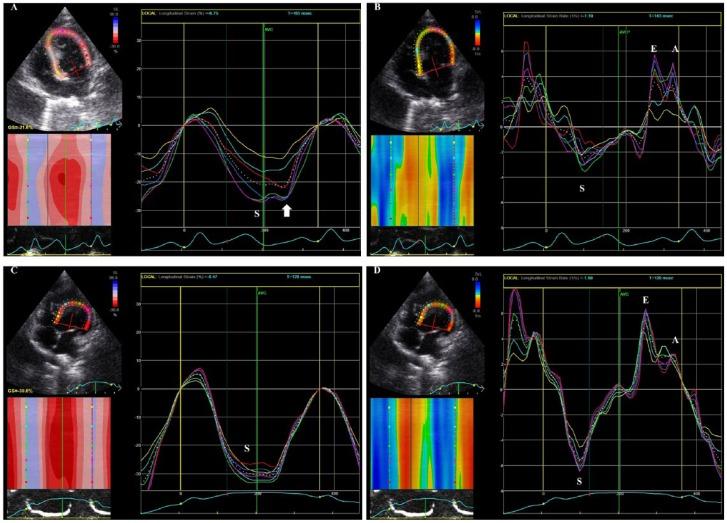

A 5-month-old intact female Scottish Fold cat was presented for cardiac evaluation. Careful auscultation detected a slight systolic murmur (Levine I/VI). The findings of electrocardiography, thoracic radiography, non-invasive blood pressure measurements and conventional echocardiographic studies were unremarkable. However, two-dimensional speckle tracking echocardiography revealed abnormalities in myocardial deformations, including decreased early-to-late diastolic strain rate ratios in longitudinal, radial and circumferential directions, and deteriorated segmental systolic longitudinal strain. At the follow-up examinations, the cat exhibited echocardiographic left ventricular hypertrophy and was diagnosed with hypertrophic cardiomyopathy using conventional echocardiography.

This is the first report on the use of two-dimensional speckle tracking echocardiography for the early detection of myocardial dysfunction in a cat with hypertrophic cardiomyopathy; the myocardial dysfunction was detected before the development of hypertrophy. The findings from this case suggest that two-dimensional speckle tracking echocardiography can be useful for myocardial assessment when conventional echocardiographic and Doppler findings are ambiguous.